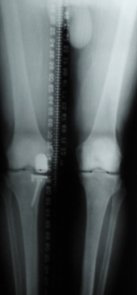

On recherche essentiellement à l’examen : une désaxation de la jambe constitutionnelle mais aussi liée à l’usure du cartilage, une perte de mobilité en particulier de l’extension, une perte musculaire (amyotrophie) qui traduit une sous utilisation du genou. On détermine également un retentissement du genou atteint sur le dos, la hanche ou la cheville.

L’étude des radiographies analyse la déformation réelle, les articulations sus et sou jacente et le degré d’usure. Il est important de préciser que l’indication de prothèse se pose dans la majorité des cas devant un bilan radiologique standard. Une IRM ne doit donc pas être le principal examen.

Désaxation et perte d’extension